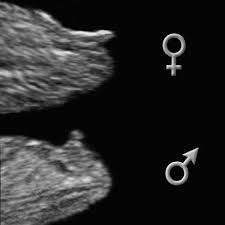

опытный узист увидит разницу "полового бугорка"

у мальчиков угол от спины до кончика бугорка более 30 градусов, у девочек менее)